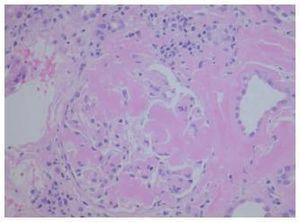

En la ecografía renal se detectó un injerto de 13,2 x 6,2 cm, con parénquima y ecoestructura conservada sin evidencias obstructivas. El 23 de mayo de 2009 se realiza biopsia renal obteniéndose 25 glomérulos en los que se observó una cantidad variable de un material amorfo eosinófilo, que en la mayoría de los glomérulos se deposita en el penacho glomerular y se extiende hacia el resto. Dicho material también se observa en el intersticio, alrededor de los túbulos y en el espesor de la pared de vasos, haciendose aún más patente con la tinción Rojo Congo con brillo en verde manzana bajo luz polarizada (figura 1). Con pretratamiento de permanganato potásico, se pierde en la tinción para Rojo Congo. Se observan también túbulos con epitelio edematoso y un infiltrado inflamatorio crónico poco marcado en el intersticio, constituido por linfocitos de pequeño tamaño. El estudio de inmunofluorescencia resultó negativo. El diagnóstico anatomopatológico fue de amiloidosis secundaria tipo AA. Mediante ecocardiografía se descartó la existencia de una miocardiopatía infiltrativa, así como la infiltración en otras localizaciones. El 25 de junio, 3 meses después del inicio del cuadro, la paciente comienza terapia renal sustitutiva, falleciendo a los 6 meses por hemorragia cerebral en el contexto de plaquetopenia e intolerancia al injerto.

Figura 1. Amiloidosis en glomérulo de biopsia renal.